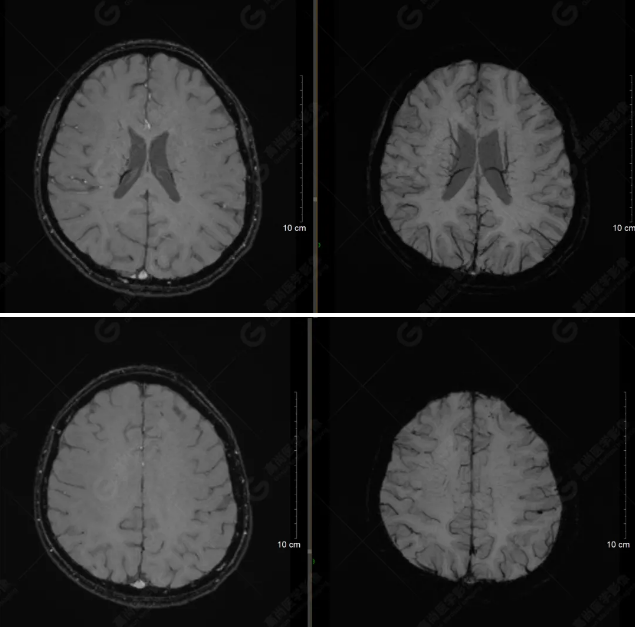

顱腦MRI平掃未見明顯異常,左側(cè)乳突內(nèi)積血,建議補(bǔ)充SWI檢查。(左側(cè)為薄層原始圖像,右側(cè)為后處理5mm圖像)

左側(cè)額底及左側(cè)顳葉內(nèi)見多發(fā)斑點狀極低信號影??紤]額顳葉多發(fā)腦挫傷伴微出血、含鐵血黃素沉著,左側(cè)乳突骨折、乳突內(nèi)積血。討論:1、SWI利用不同組織間磁敏感的差異成像并將其放大,通過檢測病灶中的靜脈分布、出血灶和礦物質(zhì)沉積等,有效改善了相關(guān)疾病的診斷,主要應(yīng)用于中樞神經(jīng)系統(tǒng)。2、根據(jù)磁距圖像和相位圖像表現(xiàn),對于鑒別顱內(nèi)出血及鈣化有一定程度的價值,用于彌補(bǔ)MRI對鈣化顯示的不足。